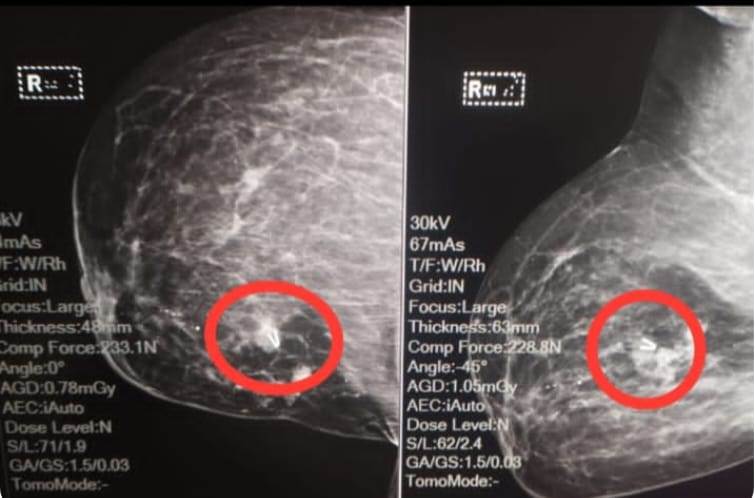

نجح الفريق الطبي بمستشفى كفر الدوار العام فى اجراء جراحة متقدمة بتركيب كليبس لورم بالثدي باستخدام الأشعة الداخلية

وأجرى الفريق الطبي بمستشفى كفر الدوار العام لأول مرة في مستشفيات البحيرة ، عملية تركيب كليبس لورم بالثدي باستخدام الأشعه الداخلية بالمستشفي بواسطة الدكتور مصطفي محمد عبدالحميد استشاري ورئيس قسم الأشعة التشخيصية والتداخلية بمعاونة الدكتورة أمنيه الركايبي أخصائي الأشعة ، وذلك لمريضة تتلقي العلاج الكيماوي بالمستشفي تحت إشراف الدكتور ماهر سليمان وتحت إشراف الدكتور أحمد خضر مدير المستشفى.